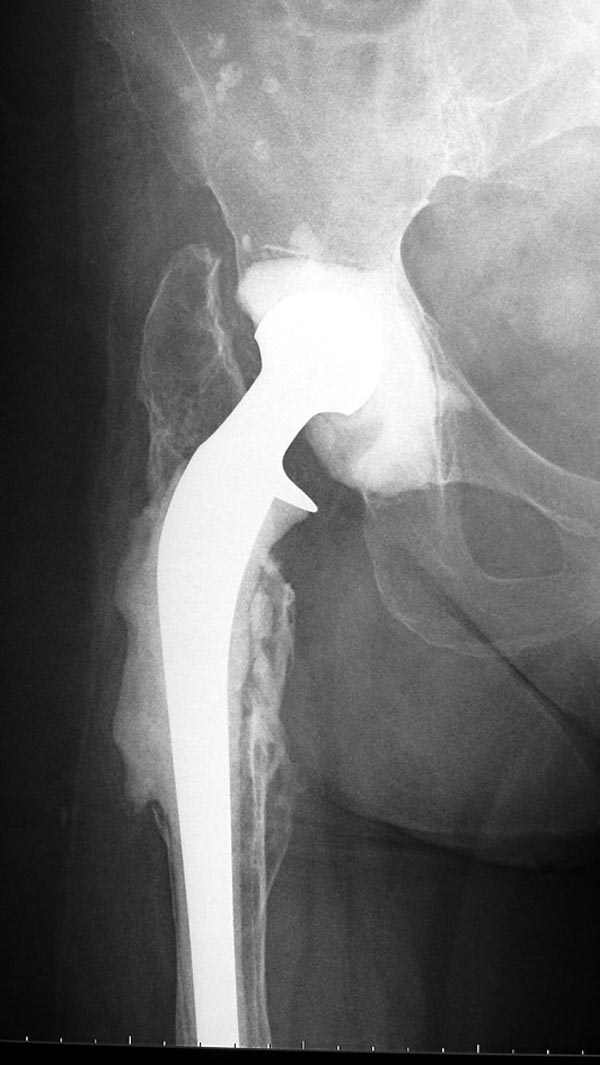

Из предложенных вариантов быстрейший результат можно ожидать после поэтапного эндопротезирования.

"Антибиотико-цементные" спейсеры после купирования

инфекции уже после первого этапа позволяют больным

передвигаться самостоятельно, иногда нагружая конечность годами.

В вертлужную полость устанавливается цемент и головкой протеза выдавливается выемка, т.е. создается место для головки. В проксимальное бедро устанавливается заранее подготовленный цементный бедренный компонент.

Через пару месяцев после улучшения мягкотканой

кондиции можно приступить к окончательному протезу.